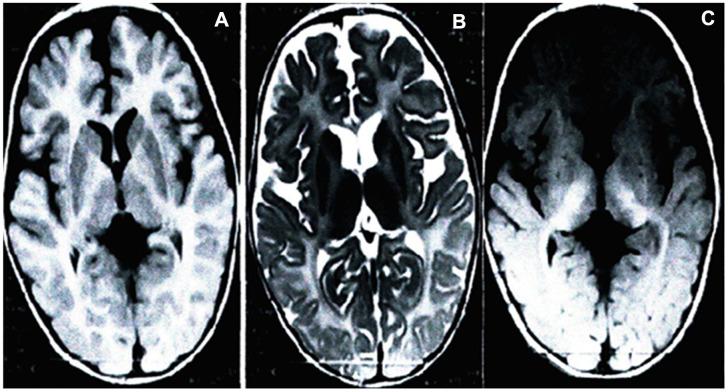

对患有 Pelizaeus-Merzbacher 病的一家系应用单核苷酸多态性微阵列进行产前诊断。

Prenatal diagnosis of duplication by single nucleotide polymorphism array in a family with Pelizaeus-Merzbacher disease.

A family with a history of Pelizaeus-Merzbacher disease (PMD) received prenatal diagnosis of gene duplication in a fetus using a single nucleotide polymorphism (SNP) array. A 27-year-old pregnant woman was referred for genetic counseling due to her four-year-old son being diagnosed with a suspected classic type of PMD. Amniocentesis was performed at 18 and 3/7 weeks of gestation, and the SNP array was carried out on DNA from the mother, her affected son, and fetus, then further confirmed by multiplex ligation-dependent probe amplification (MLPA). Cytogenetic analysis of the fetus showed 46,XY. SNP array analysis revealed that the male fetus did not carry gene duplication but the affected boy did, and the mother was a carrier for the duplication of the gene. All SNP array results were further confirmed by MLPA. SNP array and MLPA analyses of peripheral blood verified the nonduplication of the gene in the infant after birth. At present, the child (without duplication) is developing normally. This study preliminarily suggests that SNP array is a sensitive and accurate technology for identifying duplication and is feasible for reliable diagnosis, including for the prenatal diagnosis of PMD resulting from duplication.

摘要